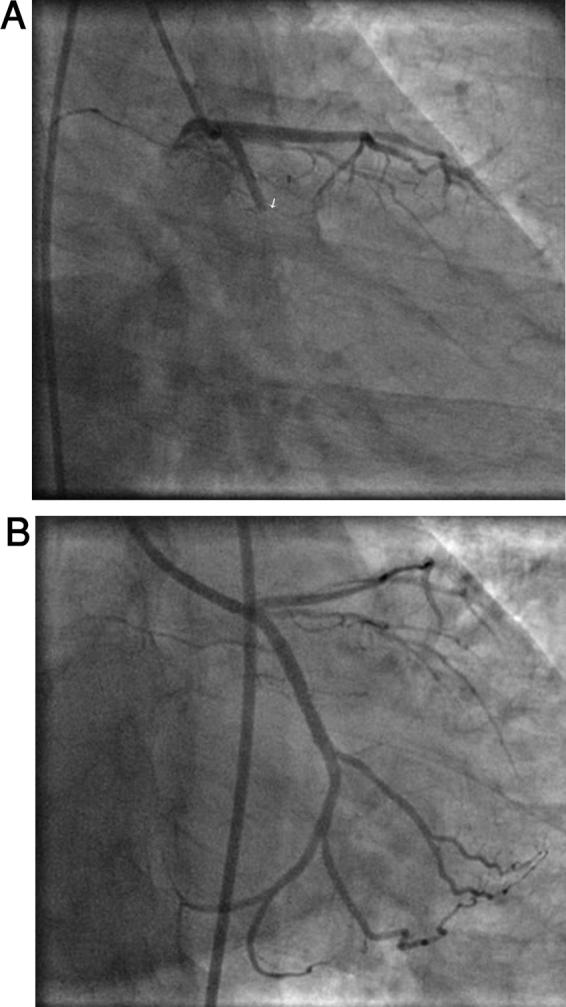

Acute coronary syndrome (ACS) and electrocardiography showing ST elevation in Lead aVR>V1 are considered specific for left main coronary artery lesion and also suggest extensive anterior wall myocardial infarction. In this backdrop, we are presenting an incidental observation of an association of ST elevation in lead aVR>V1 in isolated proximal left circumflex lesion in the setting of ACS, who later underwent successful primary percutaneous coronary intervention.

急性冠状动脉综合征(ACS)以及心电图显示aVR导联ST段抬高大于V1导联,被认为是左主干冠状动脉病变的特异性表现,也提示广泛前壁心肌梗死。在此背景下,我们报告1例ACS患者,其孤立性左旋支近端病变时出现aVR导联ST段抬高大于V1导联,该患者随后成功接受了直接经皮冠状动脉介入治疗,此为一偶然发现。